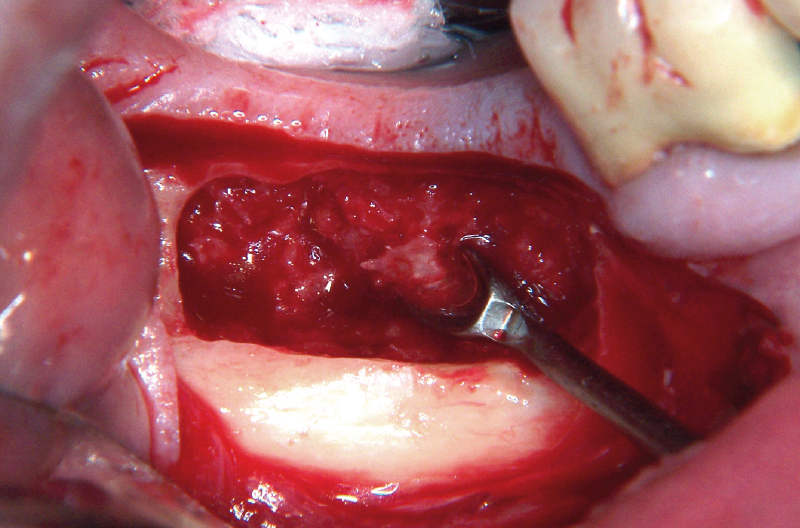

Con il termine di peri-implantite intendiamo un processo infiammatorio attorno agli impianti associato a significativo e progressivo riassorbimento osseo (EAO 2012). L’eziologia primaria è dovuta ad infezione batterica (Mombelli 2002) (Figg. 8, 9). Il caso di seguito riportato è stato trattato con un approccio chirurgico di osteoplastica e implantoplastica (Fig. 10). Tale approccio può essere utilizzato nelle zone non a valenza estetica e come trattamento di temporeggiamento. Ulteriori informazioni sulla metodica possono essere reperite nel libro: “L’impianto singolo: dalle evidenze scientifiche ai risultati clinici”; ISO Edizioni, ottobre 2014, pag.170-173.

- Fig. 8 – Perimplantite: l’apertura di un lembo permette di evidenziare la perdita crateriforme di tessuto osseo perimplantare. Il tessuto infiammatorio è già stato rimosso